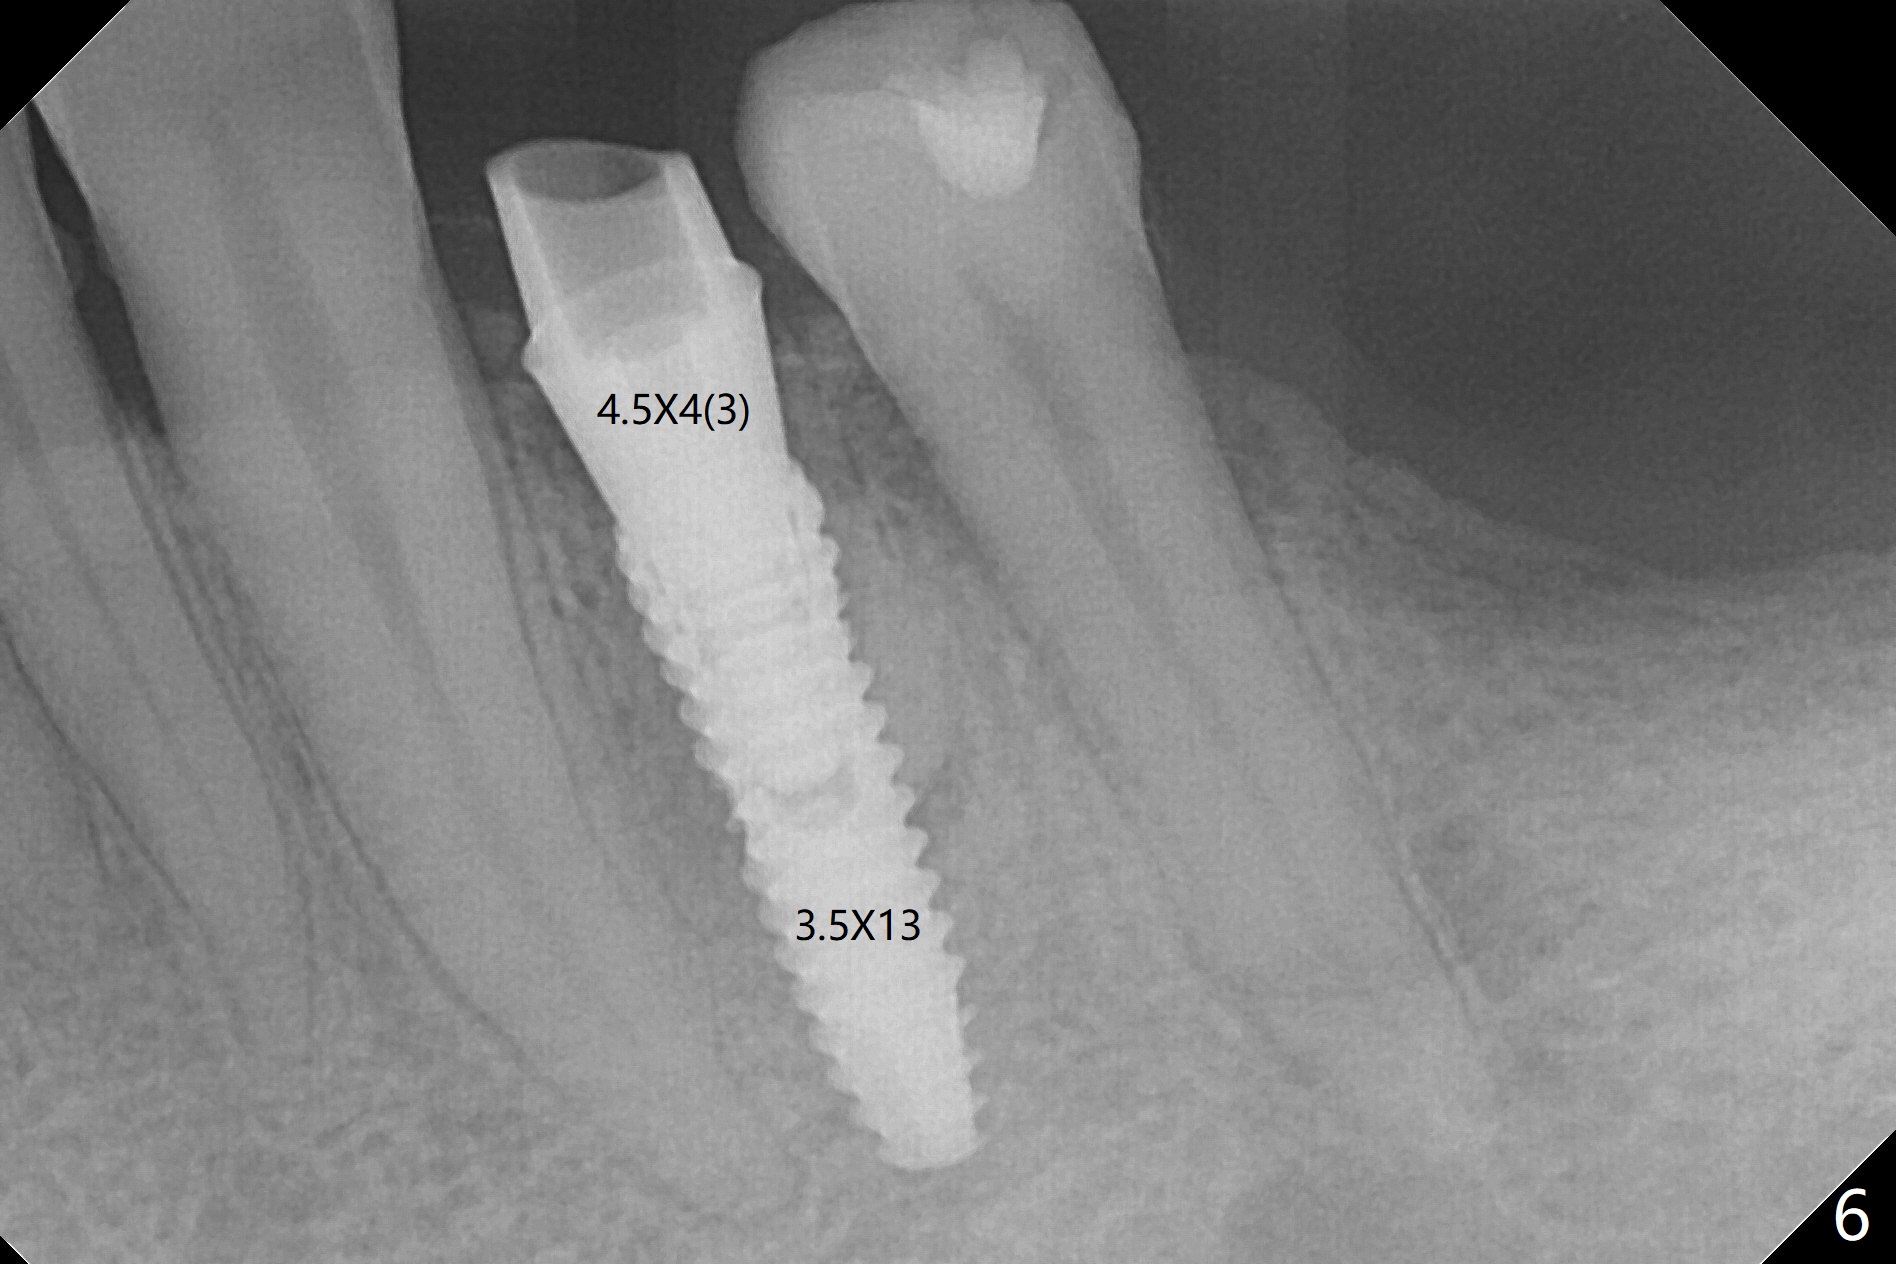

Since the root surface at #29 is distinct (Fig.1), while that at #21 is not (with subgingival caries, Fig.2), closed and open socket shields are done at #29 and 21, respectively (Fig.3,4 S), followed by implant placement with guide (Fig.4-6). With socket shield, there is limited remaining space for bone graft (Fig.4). The shield associated with the closed technique is exposed nearly 2 months postop (Fig.7), while the one associated with the open technique is not (Fig.8). The buccal plate is minimally atrophic with either technique.